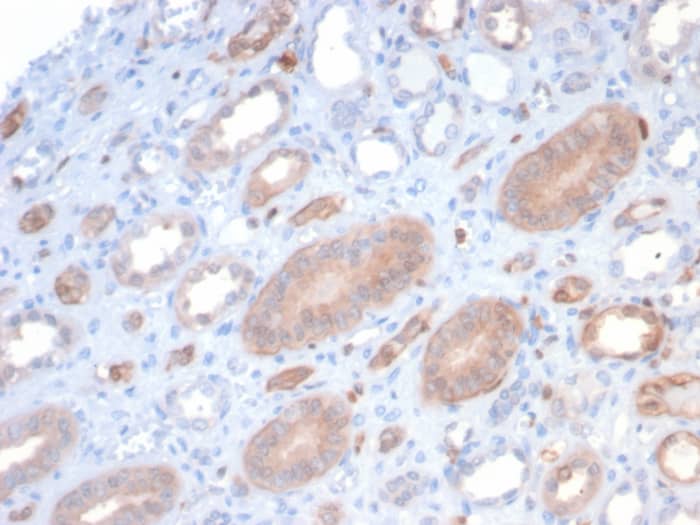

Scientific Data Images for S100P Antibody (S100P/7373)

Formalin-fixed, paraffin-embedded human kidney stained with S100P Recombinant Mouse Monoclonal Antibody (S100P/7373). HIER: Tris/EDTA, pH9.0, 45min. 2: HRP-polymer, 30min. DAB, 5min.S100P Antibody (S100P/7373) - Azide and BSA Free